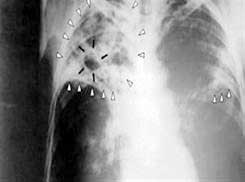

Hình chụp phổi

Ngoài việc chụp hình quang tuyến X hay thử đờm để xem b ệnh lao đã tấn công phổi hay chưa , bệnh lao còn có thể được truy tầm bằng cách thử da Tuberculin ( xét Nghiệm Mantoux) để biết một người đã bị nhiễm khuẩn hay chưa . Kết quả thử nghiệm da có được trong vòng từ 48 đến 72 tiếng. Nếu thử nghiệm dương tính thì bệnh nhân phải được điều trị cho tới cùng nếu không hệ miễn nhi ễm sẽ bị suy yếu. Thuốc men hỗ trợ cơ thể chống lại các vi khuẩn và giảm rủi ro bệnh phát tác